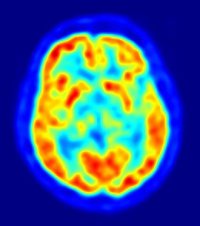

Identifican el azar como actor fundamental en la formación del cerebro

Cerebro

Investigadores del Instituto de Neurociencias de Alicante han determinado que el azar es un actor fundamental en el desarrollo del cerebro, cuando en la etapa en la que se forman los órganos las neuronas migran desde zonas más internas del encéfalo hacia la superficie.